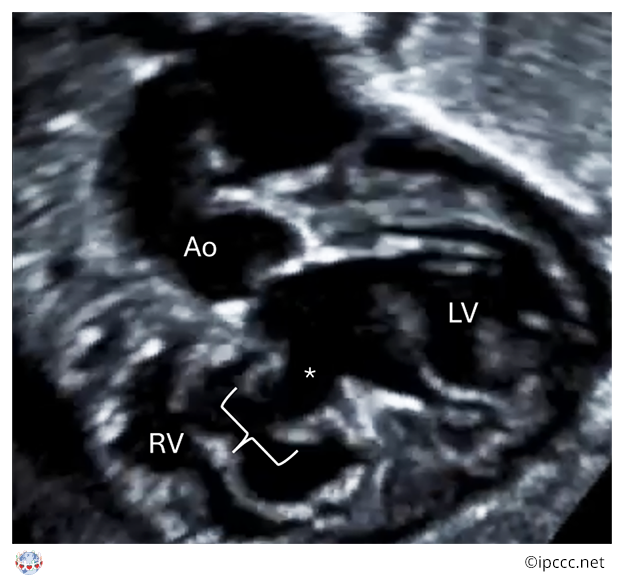

A congenital cardiac malformation in which there is a ventricular septal defect that usually, but not always, extends beneath the full annular length of the septal leaflet of the tricuspid valve and to the membranous septum, into the inlet component of the right ventricle in the absence of atrioventricular septal malalignment and of a common atrioventricular junction.

Echocardiogram